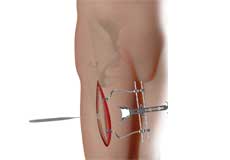

Proximal Hamstring Repair

These muscles help in extending your leg and bending your knee. Therefore, any damage to the hamstring muscle group affects both hip and knee movements.